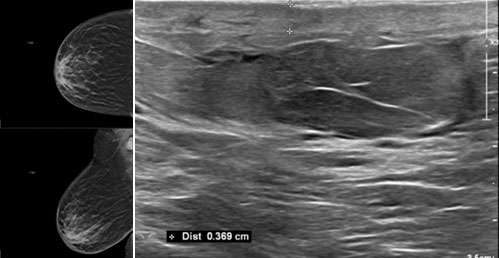

Often, the diagnosis of inflammatory causes of breast skin changes can be made on clinical grounds. When imaging is performed, mammographic and ultrasound findings are nonspecific and similar to the findings listed above for infection of the breast (Figure 1). The role of imaging in these cases is to evaluate for or exclude malignancy.

The mammographic findings of Paget’s disease include skin thickening in the nipple areolar complex region, nipple retraction, underlying suspicious calcifications, or a discrete mass. The ultrasound findings include nonspecific heterogeneity of the breast parenchyma, a mass, dilated ducts, and skin thickening or hypervascularity in the nipple areolar complex (Figure 3). Breast MRI may assist in further evaluation in the setting of negative mammogram and ultrasound findings (Figure 4).